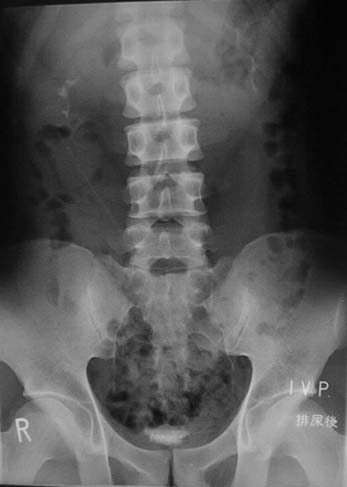

排尿後の写真

ふつうはおしっこが終わると膀胱は空になります。

このときの残尿の状態などを見ます。